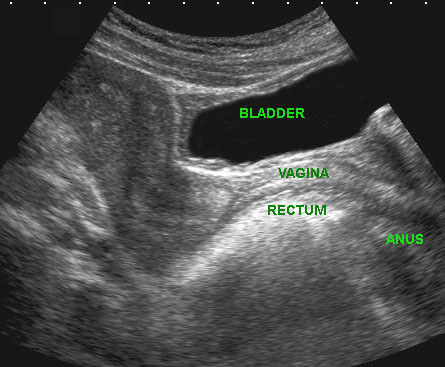

Trên mặt phẳng đứng dọc có thể xác định được tử cung, cổ tử cung, âm đạo, trực tràng hậu môn và niệu đạo (u.), cũng như túi cùng trước và túi cùng sau của âm đạo ở trạng thái xẹp.